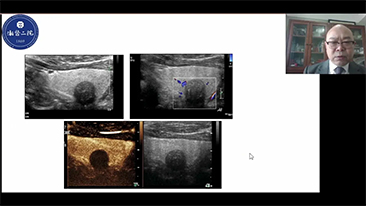

Hoe duidelijk is een lever te zien?

Bij focale leverlaesies, zoals hemangioom of leverkanker, speelt ultrasone contrastbeeldvorming een belangrijke rol. Ultrabrede niet-lineaire UWN+ contrastbeeldvormingstechnologie kan helpen bij het verkrijgen van een betere penetratie, een hogere contrast-weefselverhouding, met een lagere MI en een langere observatie van de perfusietijd.